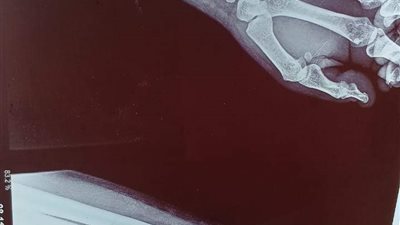

علاج كسر مفتت في عظمة الكعبرة لأول مرة بمستشفى أشمون العام